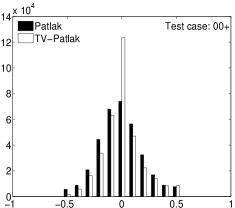

In the images shown in the figures we illustrate the calculated uptake rates of the FDG. Images for the CMRGlc can be obtained by directly scaling . In figure 1 we compare the result of using Patlak and TV-Patlak for estimating the uptake rates with respect to no noise, noise in the input function, Poisson noise in the sinogram, and finally with respect to the case in which the irreversibility assumption is violated but without noise in the sinogram or input data. In each case the histogram of the relative errors is given on the left, the Patlak image in the middle and the TV-Patlak on the right. The different scales in the histograms are due to the total number of results illustrated. When there is no noise (triples and ) the histogram illustrates results over all voxels but only one simulation, while for the noisy simulations the results are for all voxels over all realizations of the noise. The TV-Patlak images are more homogeneous in all cases and the relative errors are smaller. The figures clearly show the improvements of employing the TV-Patlak method as compared to using Patlak independently for each voxel. This is confirmed in figure 2 in which images with noise in the sinogram, positive and different noise levels in the input function are shown.

Quantitative measurements, confirming the illustrations, are presented in table 3. There we also present the results for conventional Patlak’s method with post-smoothing by two standard filters:

Consistent with the observation in [21, 16], we find that violation of the Patlak assumption, , introduces about bias; when but for . The rows (std) and “# 10% (#15%)” provide complementary supporting information, indicating that the TV is minimized by TV-Patlak; as compared to Patlak, Patlak-GF and Patlak-MF the number of voxels with larger error is reduced. In particular, we emphasize that TV-Patlak provides a better noise removal mechanism than popular post-filtering approaches.

In figures 3 and 4 we illustrate the uptake rates and relative error in the uptake rates, respectively, calculated by Patlak, TV-Patlak, Patlak-GF and Patlak-MF for one simulated data case , i.e. , noise in the input function and Poisson noise in the sinograms. The uptake rate image generated by Patlak-MF is visually smoother than that by TV-Patlak, but the equivalent histograms show that the relative error is higher for Patlak-MF than for TV-Patlak; the Patlak-MF image is over-smoothed.